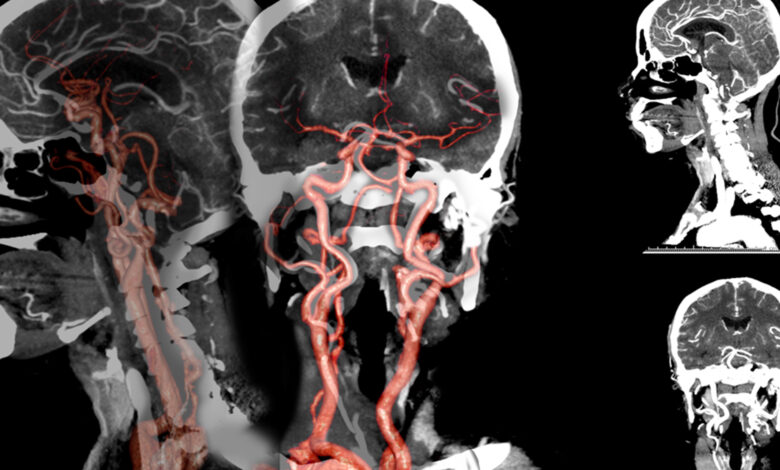

سیتی آنژیو چیست عبارت «آنژیوگرافی» یا «تصویربرداری از رگ ها» برگرفته از دو کلمه آنژیو=رگ و گرافی=تصویربرداری است. به طور معمول و به بیان ساده برای دیدن اندام های داخلی بدن اغلب از اشعه X استفاده می شود.

این اشعه در عبور از بافت های نرم بدن جذب نشده و به راحتی می تواند از بدن عبور کند. اگر در زمان عبور اشعه ایکس از رگ ها، یک ماده حاجب و جذب کننده اشعه ایکس به آن قسمت تزریق شود، اشعه X در محل مورد نظر جذب می شود.

در نتیجه این اقدام، تصویر قسمت موردنظر به صورت کنتراست و متمایز از بافت های اطرافش در تصاویر رادیولوژی قابل مشاهده خواهد بود.با استفاده از این روش می توان تصاویر داخل عروق بدن مانند شریان ها یا وریدها را به همراه ماده حاجب رادیولوژی به دست آورد و بیماری را تشخیص داد.

با استفاده از سی تی آنژیوگرافی می توان بیماری های عروقی مانند انسداد رگ یا وجود لخته در داخل رگ را به خوبی و با دقت بالا تشخیص داد. این روش تصاویر و یا حتی فیلم تهیه شده از حرکت ماده حاجب در داخل عروق به صورت دیجیتال قابل ذخیره سازی و انتقال است و پزشک معالج می تواند آن را از طریق نرم افزار مشاهده و تحلیل کند.

سی تی آنژیوگرافی در ارزیابی عروق و شریان ها و اندام هایی که توسط آنها تغذیه میشوند، کاربرد دارد مانند: مغز، قلب، لگن، گردن، قفسه سینه، پاها و انگشتان بازوها و دستها، شکم (کلیهها و کبد).